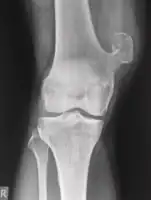

Medical imaging usually shows a well-defined wide-based bony growth on the surface of bone.[5] It can be pedunculated and irregular, giving it a "bizarre" appearance, and is not connected to underlying bone.[2]

X-ray left foot: Bizarre parosteal osteochondromatous proliferation in 2nd toe

X-ray hand, BPOP 2nd metacarpal

X-ray hand, BPOP 2nd metacarpal (side view)